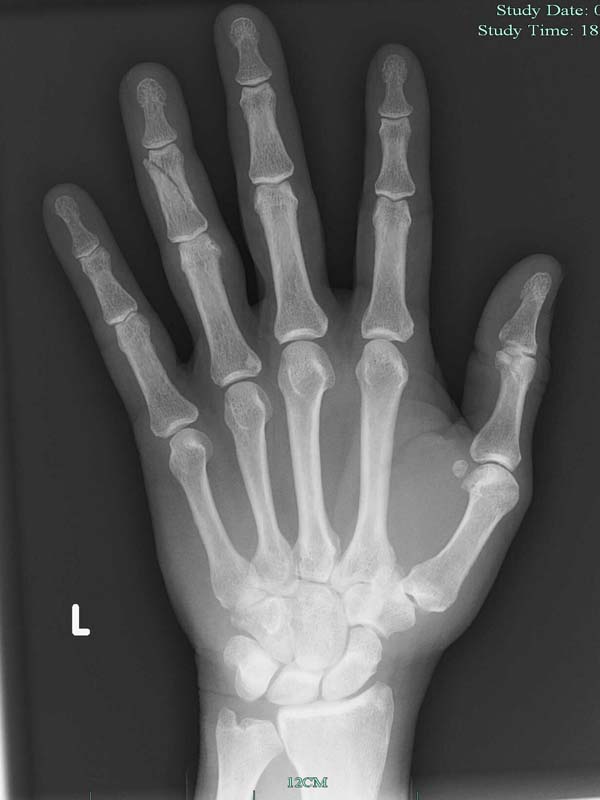

Nearly killed Tommy - be careful out there - we were aware of the unsettled weather and expecting gusty stuff last Sunday - hell I was on a 5m but surprising how quick things can go bad.

One minute it is blowing 20 and a having a casual chat while preparing to launch the last man on the beach with my kite in the air - next minute blowing 40+ and getting yarded and giving Tom the launch of death. Very scary watching Tom's kite rocket across the window and then blow away.

Toms Fracture.jpg

Bummer dude, cool x-ray though Laughing